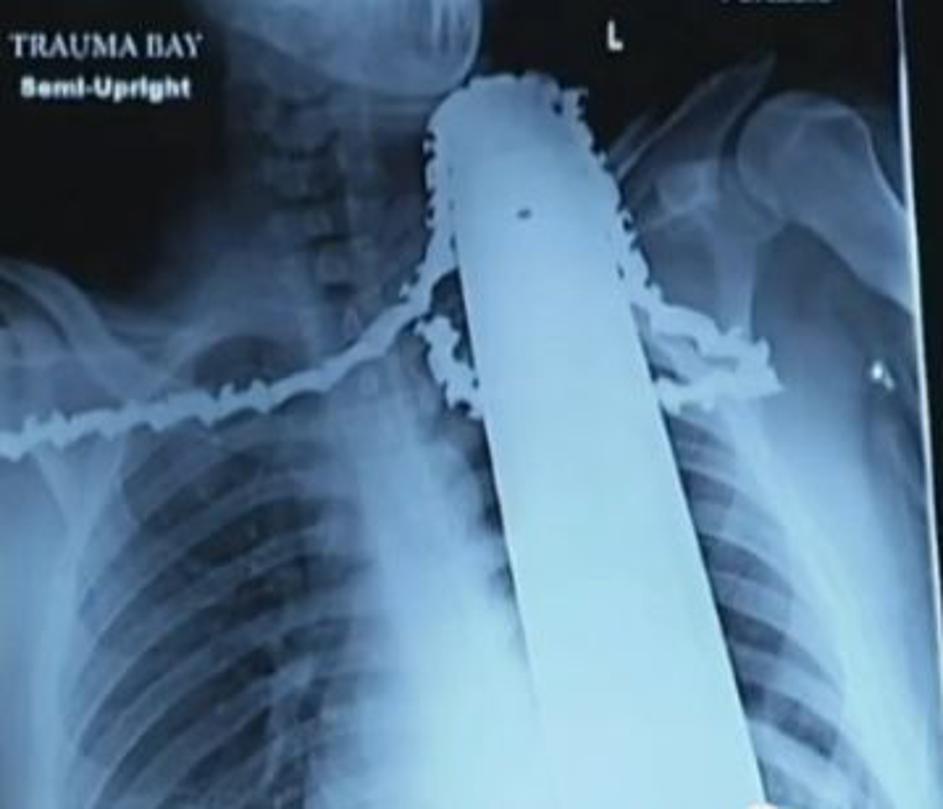

Motorka se mu je zarila v ramo in vrat

James Valentine motorna žaga nesreča Rezilo je zgrešilo vse vitalne dele in poškodovalo le ramenske mišice. Youtube James Valentine motorna žaga nesreča

James Valentine motorna žaga nesreča James Valentine bo okreval več tednov. Youtube James Valentine motorna žaga nesreča